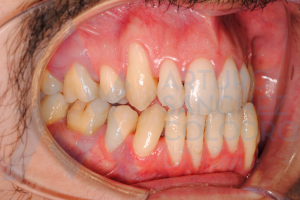

Hoy queremos compartir con vosotros el caso de éxito de un paciente que presentaba recesiones múltiples.

Estas son las imágenes obtenidas de exploración intraoral inicial: